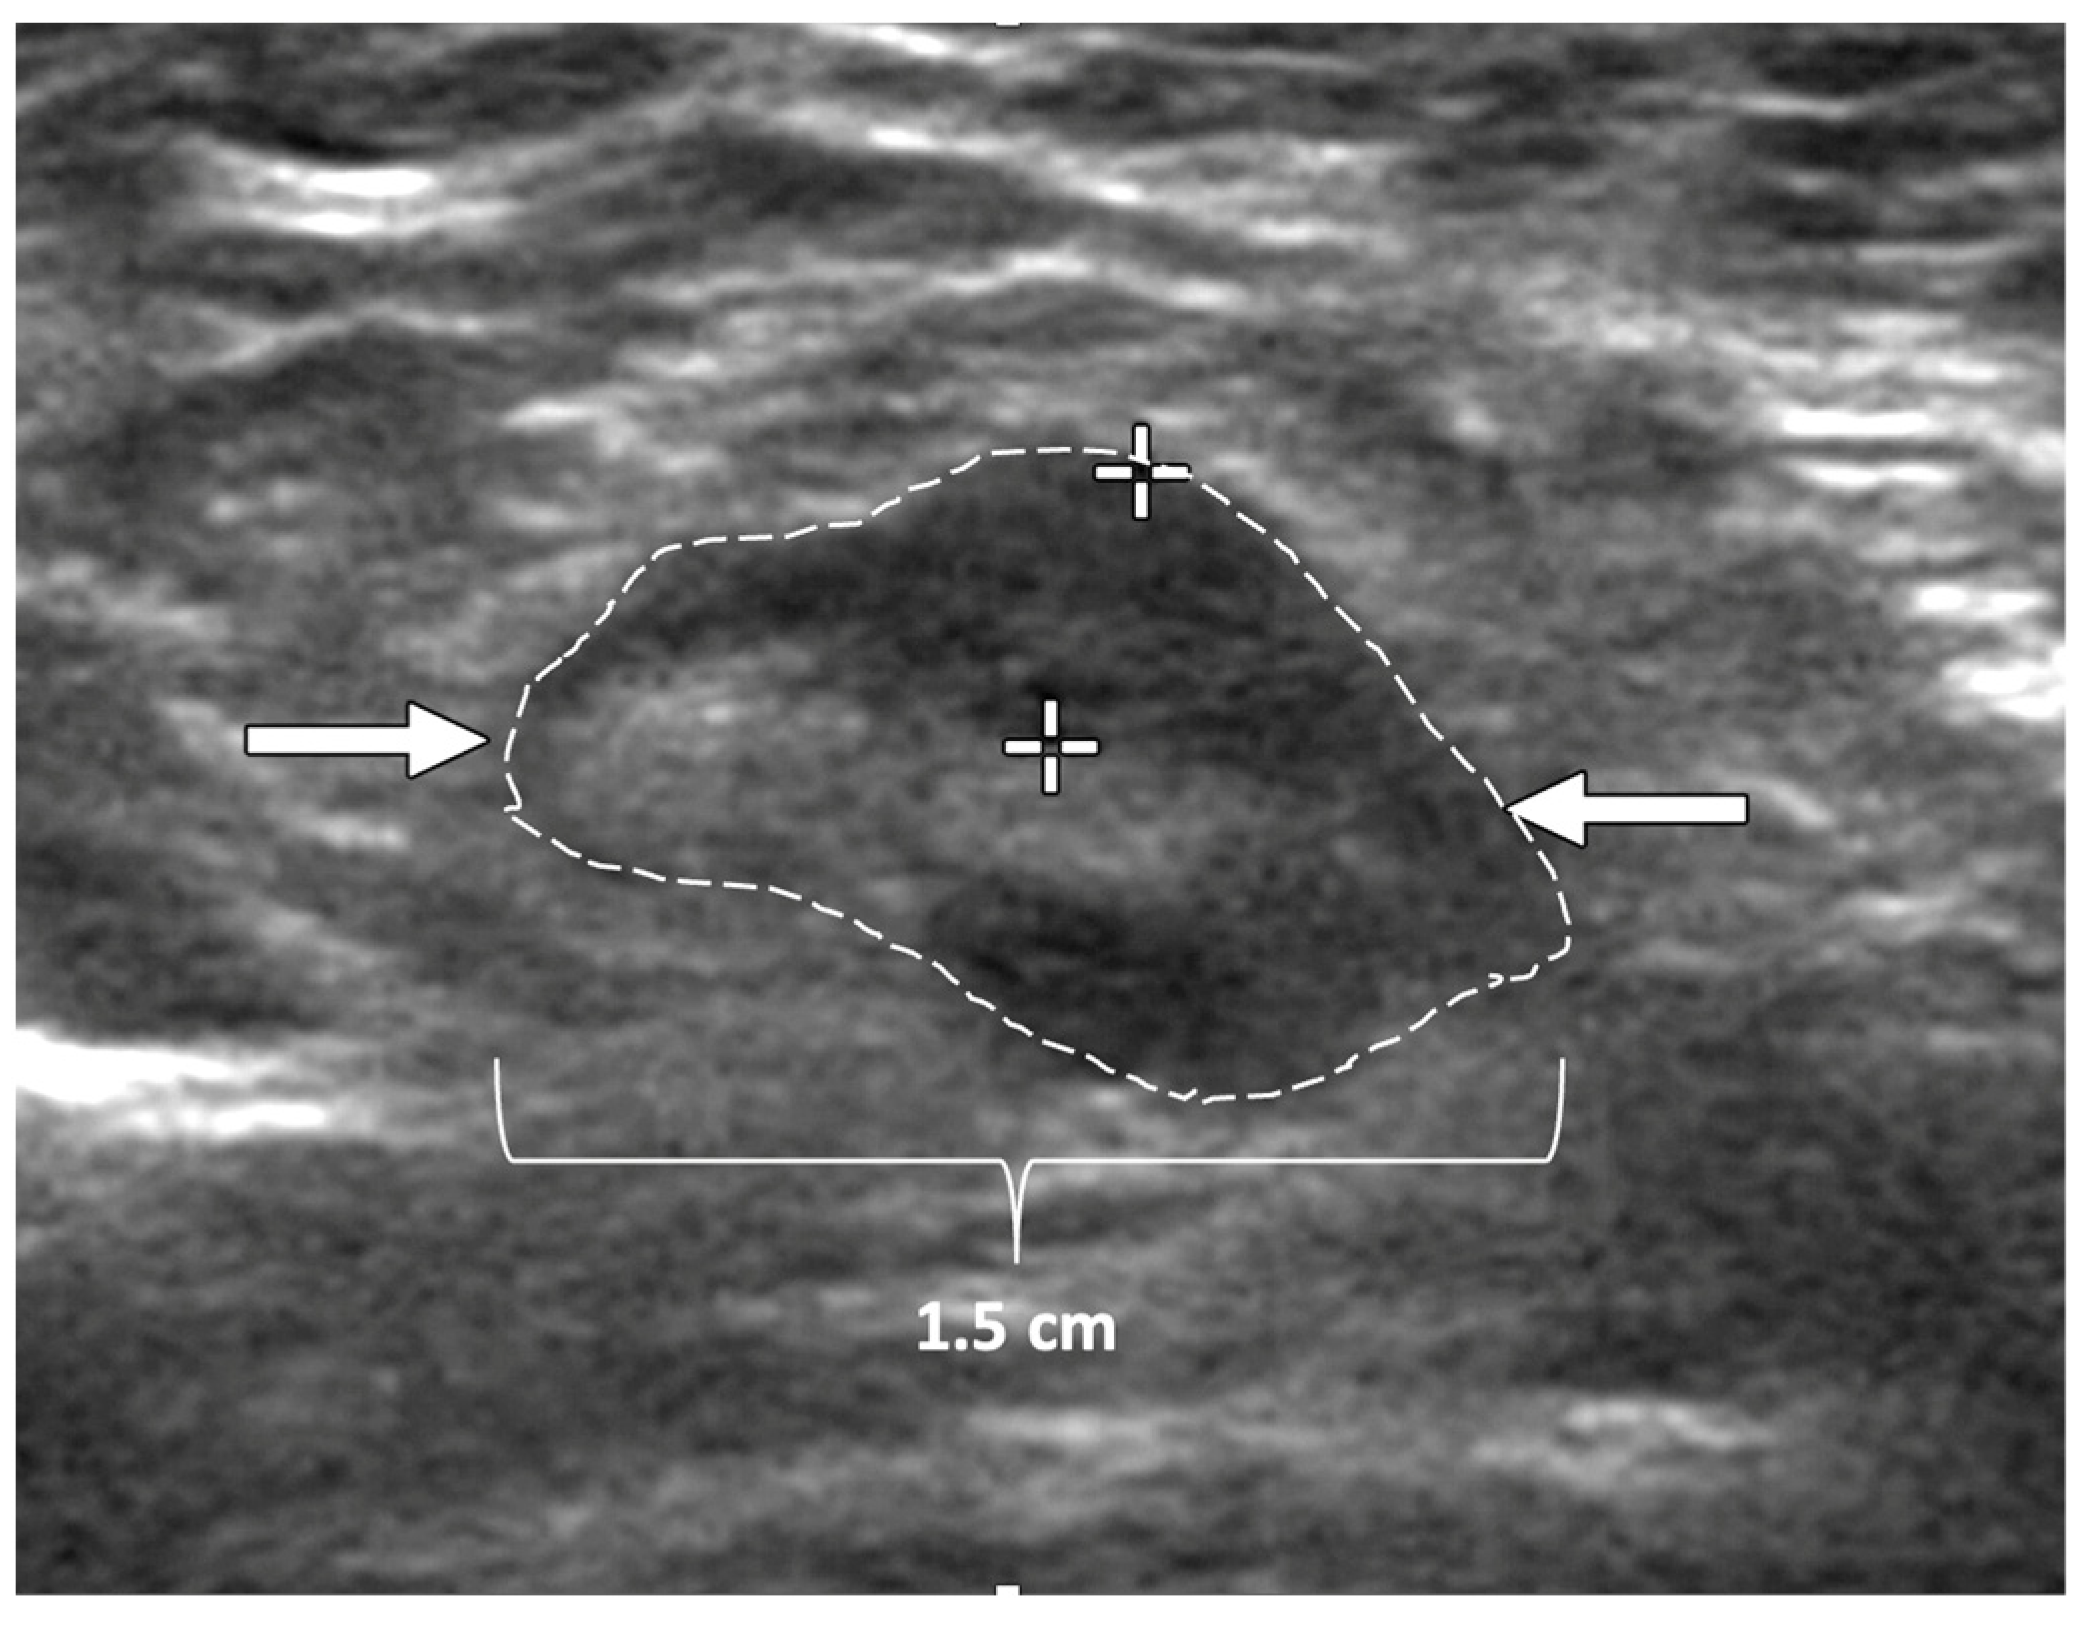

Ultrasound of the axilla. Axillary ultrasound permits the detection of abnormal appearing lymph nodes that might not be detected on physical examination, mammography, or breast MRI. Axillary ultrasound is the most sensitive imaging study for the detection of subtle changes in the shape or thickness of a lymph node cortex that might indicate the presence of lymph node metastasis (Figure 3). Detection of suspicious lymph nodes determines clinical cancer stage and requires a specific plan to manage the possibility of lymph node metastasis.

Figure 3.

Hash marks outline abnormal appearing axillary lymph node measuring 1.5 cm in maximal diameter. Paired “+” marks indicate the span of a 0.4 cm area of focal cortical thickening that is suspicious for a metastatic deposit within the lymph node.